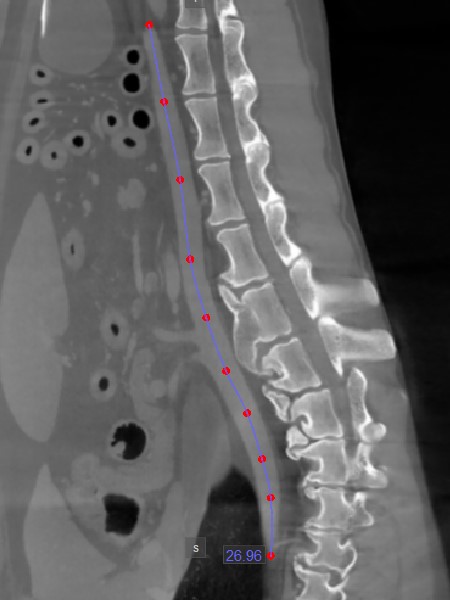

Distance

Use the Distance measurement tool to precisely measure the distance between two points with precision.

Select the Distance tool and assign it to one of the available mouse buttons. To calculate the distance, place two points on the active image slice by pressing on the appropriate position with the mouse. The distance between the two points will be automatically calculated. This tool is assigned to the middle mouse scroll button by default.

Modify the start and end point by using the Default tool from the left toolbar. The distance between the points will be automatically recalculated.

../_images/image310.jpg